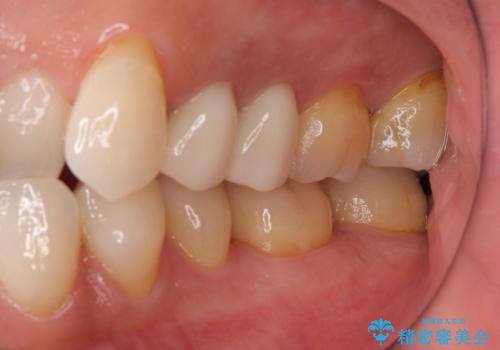

体調が悪いと腫れる 根管治療とセラミック治療

- 2年ほど放置していた左上の仮歯がとれたことをきっかけにご来院された患者様です。

セラミック治療がご希望でしたが、ときどき歯肉が腫れるということで根管治療もご希望されました。

左上で効果を実感して頂き、その後右上もご希望されました。合計3本の歯を治療しました。

左上の仮歯を2年使用して穴があいて外れたことをきっかけにご来院されました。

腫れもなくなり、見た目もきれいになったため、右上もご希望されて計3本の歯を治療しました。患者様には大変満足して頂きました。